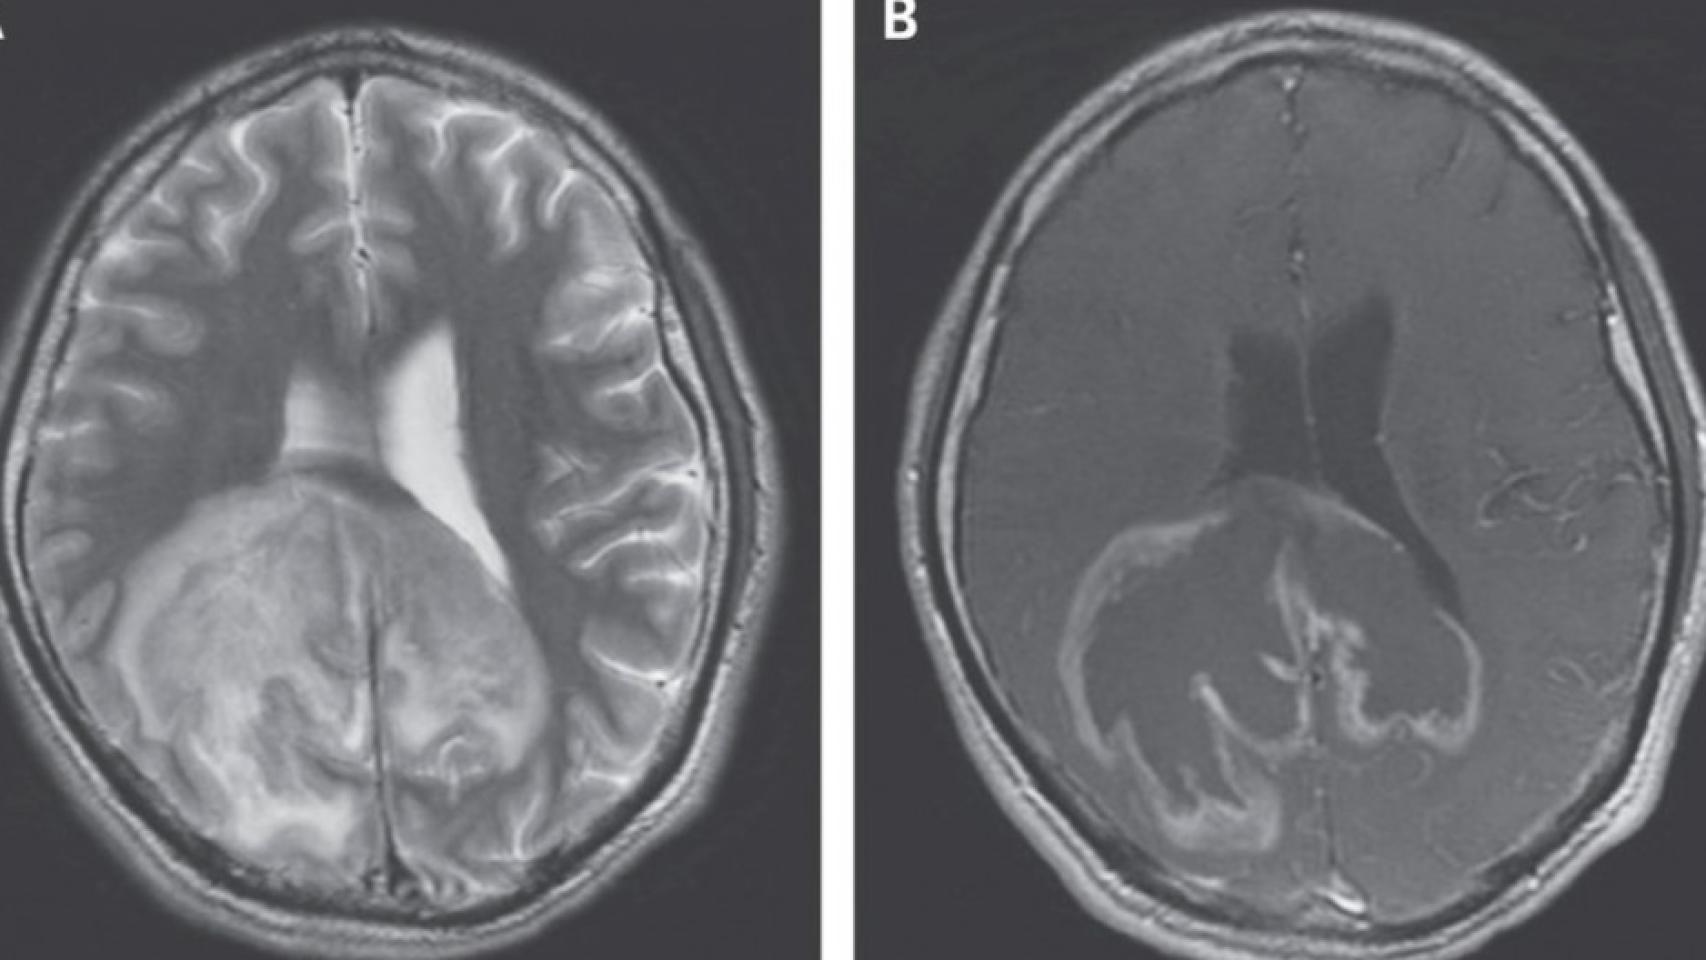

Según los autores del caso, pertenecientes a la Universidad de Stanford, al paciente se le realizó una resonancia magnética. En dicha prueba de imagen se visualizó la enorme masa cerebral, de un considerable tamaño. Asimismo, también se analizó su líquido cefalorraquídeo -la sustancia que recorre, protege y nutre al sistema nervioso central-, detectando mediante un estudio por microscopio docenas de microorganismos. Teóricamente, este líquido cerebral debe ser estéril.